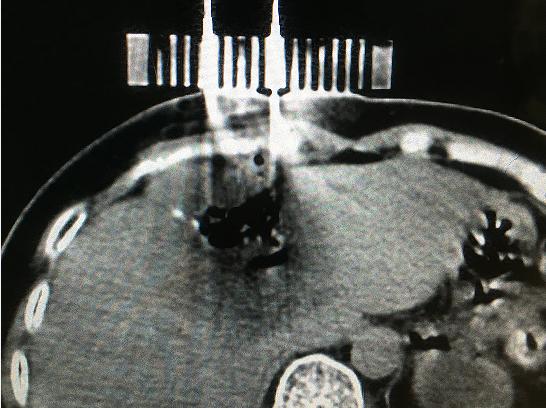

9月11日,醫院腫瘤科張開賢主任醫師團隊對一例肝癌術后復發的患者成功進行了國內首例3D打印共面模板引導下的微波消融術,標志著肝癌進入精準微波消融時代。

患者女性,57歲,肝癌術后5月復發,病灶6.0cmx6.0cm大小,位于肝臟的右葉,靠近隔頂部,經過多學科討論,決定實施經皮微波消融術,由于腫瘤體積較大,需要同時使用兩根消融天線進行多平面消融,為確保療效,兩根消融天線需要平行等距,但由于肝臟是不斷運動的臟器,徒手操作有一定技術難度,往往需要多次穿刺調整進針方向才能達到上述要求,為此,滕州市中心人民醫院腫瘤科張開賢主任醫師團隊借鑒既往采用模板引導放射性粒子植入的經驗,創造性地將3D打印模板技術應用于該例患者的消融治療,在模板引導下在兩個平面上平行等距插入兩根消融天線,經過18分鐘的消融,腫瘤完全壞死,達到完全消融,患者正在術后康復之中。

3D打印模板引導消融的優點:迅速將腫瘤與模板“固定”,防止因肝臟運動導致的穿刺不確定性;確保兩根消融天線平行等距,使熱場分布更加均勻;一次性穿刺布針成功,避免反復穿刺導致的腫瘤種植性轉移;模板對消融天線起到固定,防止因來回移動導致的消融天線位置的改變。據悉,這是國內首例3D打印模板引導下的肝癌微波消融術,這一技術的推廣應用必將造福更多的腫瘤患者。(腫瘤一科 胡苗苗)